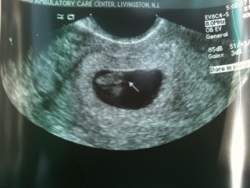

Update: we saw our little bean

and we heard the heartbeat! The arrow is pointing to his/her head and he/she is facing down. So cute, we saw the little arm and leg buds. The technician wouldn't tell me if everything was growing on schedule because the doc has to look at the pics so def still need fingers crossed. But she did say that the heartbeat was normal